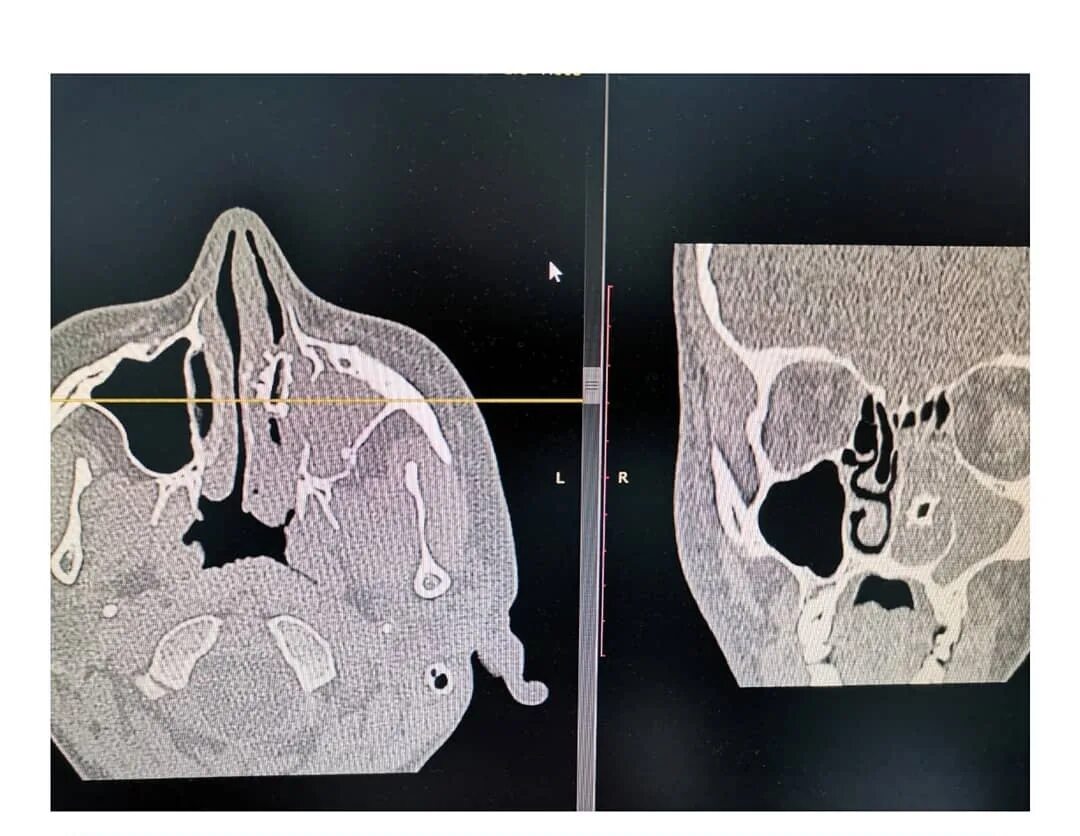

Кленовые носики на носу. носики из клена. клен на нос. кленовые семена на носу.Семечко носКленовые носики на носу. носики из клена. клен на нос. семечка от клена на нос.Инородное тело в носу у ребенка. инородный предмет в носу у ребенка. маленький нос.Семечко носИнородное тело лего в носу. у детей инородное в носу.Носики из клена. вертолетики на носу. носики клена на носу. клен на нос.Анатомия носа хрящи носа. хрящевой скелет наружного носа. сошниково-носовой хрящ анатомия.Семечко носКостная перегородка полости носа анатомия. полость носа анатомия кости.Ринолит полости носа рентген. инородные тела носа рентген. инородный предмет в носу.Инородное тело в носу у ребенка. инородное тело в носу симптомы. инородные тела полости носа. инородный предмет в носу у ребенка.Инородное тело в носу симптомы. инородные тела носа классификация. инородное тело в носу у ребенка. симптомы наличия инородного тела в носу.Семечко носКосточка вишневая в носу. возможно попадание косточки.Ребенок засунул орех в нос. вставляют детям в нос рот.Инородные тела носа первая помощь. попадание инородного тела в нос. инородных тел в ухо глаз нос. инородное тело в носу у ребенка.Семечко носВыпуклый нос.Инородные тела носа рентген. извлечение инородного тела из полости носа. перфорация носовой перегородки.Семечко носИнородное тело полости носа удаляют. удаление инородного тела из носа ребенка.Семечко носГорбоносов игорь ринопластика. кривой нос у мужчин.Нос с горбинкой. убирание горбинки носа. ринопластика кости носа.Болит кость носа на переносице. грушевидное отверстие носа.Первая помощь при попадании инородного тела в нос ребенка. способы удаления инородных тел из полости носа. инородное тело в носу у ребенка. инородный предмет в носу у ребенка.Подсолнечник плод семянка. семя семянка семечка. семечко в разрезе. семянка подсолнечника в разрезе.Семена груши. семена яблока. семечко яблока. семечко от яблока.Семена яблони. семечко от яблока. семя груши. семечки от груши.Семечко носКонопляное семечко ростки. прорастание семян каннабиса. пророщенные семена конопли. пророщенное семя канабиса.Семечко носСемечко носСемечко дерева. семена деревьев. семечко и плод. семя яблока.Анатомия носа костно-хрящевая перегородка носа. назовите анатомические отделы носовой перегородки. носовая перегородка хрящ строение. костная перегородка полости носа анатомия.Семечко носАнатомия носа хрящи носа. наружный нос строение хрящи. кости и хрящи носа анатомия.Семечко носКолумелла носа операция. келоидный рубец ринопластика. искривление колумеллы носа.